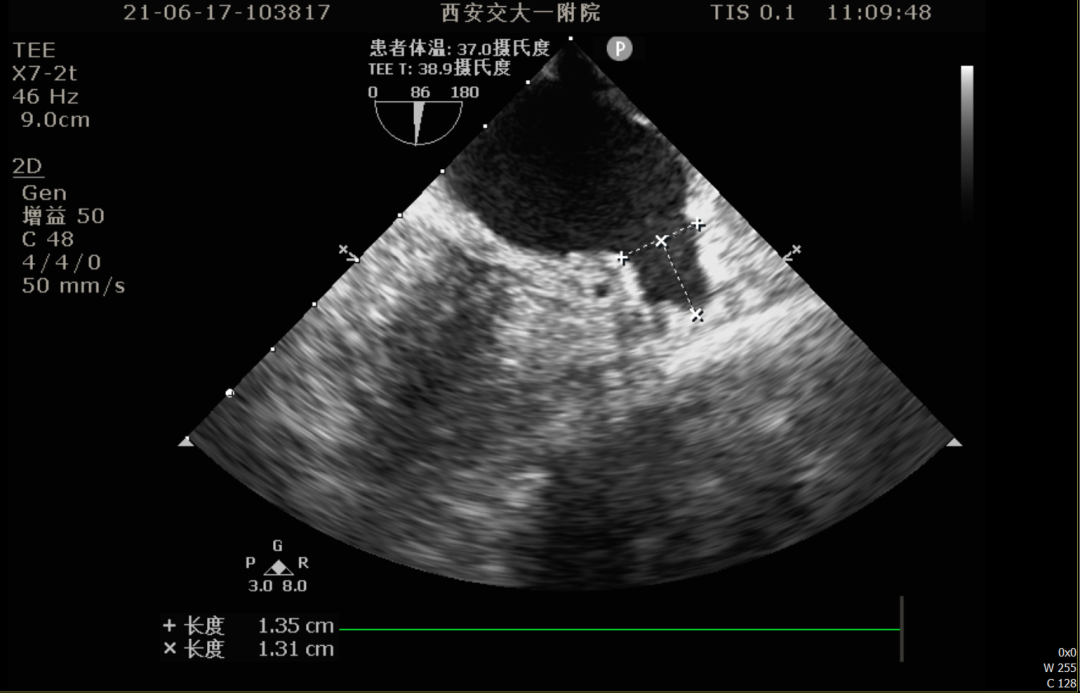

0°TEE

TEE测量左心耳数据:

TEE测量结果:

该患者左心耳开口较小,呈反鸡翅型,开口处即反折,同时内部梳状肌发达,且深度较浅,因此手术难度偏大,术前安排进一步CT评估以协助制定手术策略。